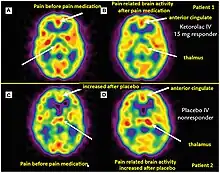

Positron emission tomography (PET) imaging in theranostics provides insight into metabolic and molecular processes within the body. The PET scanner detects photons and creates three-dimensional images that enable visualization and quantification of physiological and biochemical processes.[10] PET imaging uses radiotracers that target specific molecules or processes. For example, [18F] fluorodeoxyglucose (FDG) is commonly used to assess glucose metabolism, as cancer cells exhibit increased glucose uptake. Other radiotracers target specific receptors, enzymes, or transporters, allowing the evaluation of various physiological and pathological processes.[10]

PET imaging plays a role in both diagnosis and treatment planning. It aids in the identification and staging of diseases, such as cancer, by visualizing the extent and metabolic activity of tumors. PET scans can also guide treatment decisions by assessing treatment response and monitoring disease progression. Additionally, PET imaging is used to determine the suitability of patients for targeted therapies based on specific molecular characteristics, enabling personalized treatment approaches. [11]